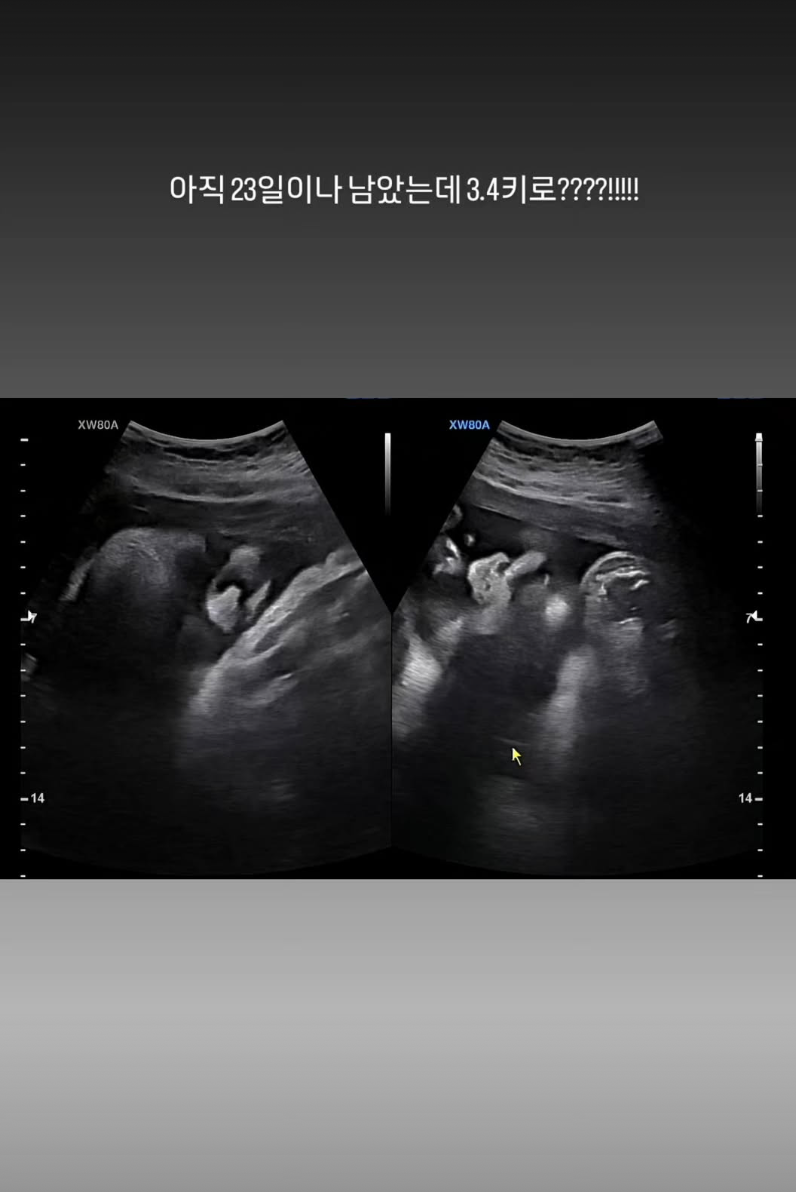

정주리는 이어 초음파 사진을 공개하기도 했는데 "아직 23일이나 남았는데 3.4kg????!!!!!"라고 말해 놀라움을 자아냈다.